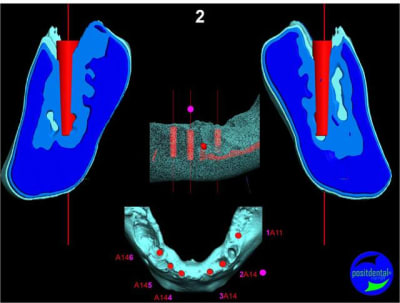

Extraction, pose d’implants Ankylos, pose des piliers Standard définitifs, mise en charge immédiate bi-maxillaire en une chirurgie.

Maxillaire inferieur – extraction 35, 34, 44, 45, 6 implants MCI, comblement osseux, bridge provisoire sans fausse gencive avec renfort métallique.

3D

Préopératoire

uniquement le scan pré-op

en attendant la pano voici les coupes de la S.I.A.O.